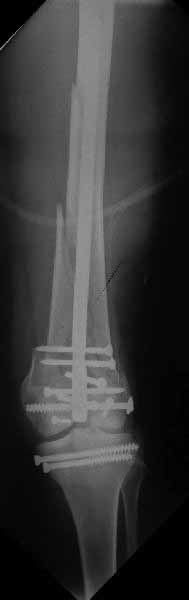

В приложении пример недавней операции, C3, открытая репозиция, фиксация мыщелков спицами и винтами, ретроградный синтез большеберцовым гвоздем 10,5 мм диаметром, винты 5 мм.

Позволю себе напомнить коллегам ещё раз, что являюсь сторонником антеградного остеосинтеза при переломах дистального эпиметафиза бедренной кости. Такая приверженность основана не на преимуществах внесуставного введения стержня или большем проценте положительных результатов. Она основана на возможности обеспечить блокирование на минимальном расстоянии от суставной поверхности в нескомпрометированной кости и, таким образом стабилизировать максимально низкие переломы. В приведенном Вами случае самый дистальный из блокирующих винтов проведен на расстоянии более 2 см от конца стержня. Из-за того, что к стержню присоединяется кондуктор, на стержне теряется 1-1,5 см его длины, где можно было разместить отверстия для блокирования. И что более важно, вместе с потерянной для этой цели длиной стержня утрачивается для размещения блокировочных винтов, пожалуй, самая ценная часть дистального эпиметафиза бедренной кости. Проблемы дистального блокирования в разных плоскостях, локализации точки ввода стержня при антеградном остеосинтезе – это всё решаемые технические проблемы. Но антеградный остеосинтез низких дистальных переломов бедра при адекватном блокировании в нескомпрометированной кости обеспечивает решение стратегической задачи – стабильный остеосинтез и возможность нагрузки.